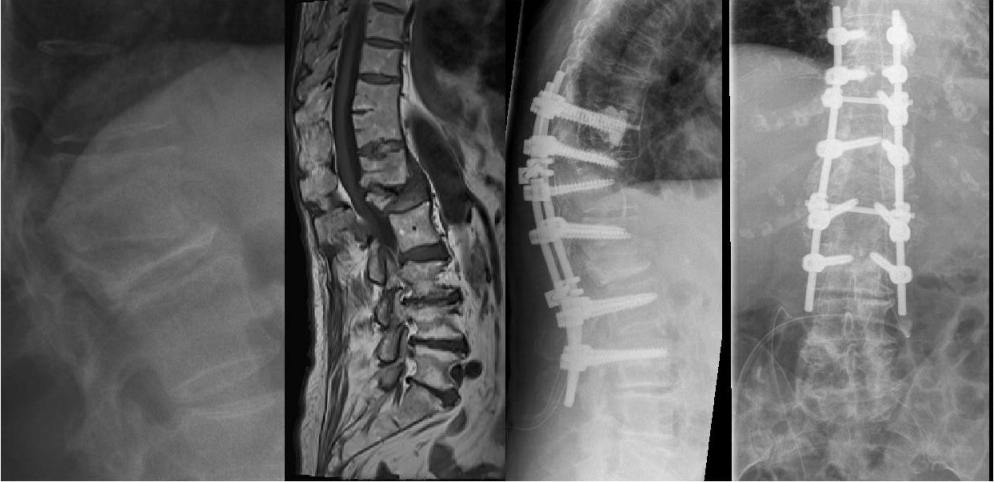

An 84-year-old female patient underwent surgery, due to a progressive kyphotic deformity and spinal cord compression after L1 fracture in severe osteoporosis 8 weeks ago. She was moved to hospital with extended wound necrosis and exogenous vertebral infection after long segment posterior stabilization. The critical soft tissue conditions and septic pedicle screw loosening required a complete implant removal. Because of the large decompression zone, an external spine fixation was necessary to ensure stability. Repetitive surgical debridement, local and systemic antibiotics and vacuum closure therapy led to soft tissue recovery and CRP normalization. The definitive internal stabilization and wound closure occurred after 4 weeks (Figure 8 [Fig. 8], Figure 9 [Fig. 9], Figure 10 [Fig. 10], Figure 11 [Fig. 11], Figure 12 [Fig. 12], Figure 13 [Fig. 13], Figure 14 [Fig. 14]).

Figure 11. Left: Complete implant removal, radically surgical debridement and external spine fixation with vacuum wound closure (Hoffmann II external fixator, 5.0 mm Pins). Right: X-ray Image of the thoracolumbar spine. External posterior stabilization.

Figure 14: X-ray image of the final internal posterior stabilization (Longitude, Medtronic; cement-augmented pedicle screws, 7.5 mm)